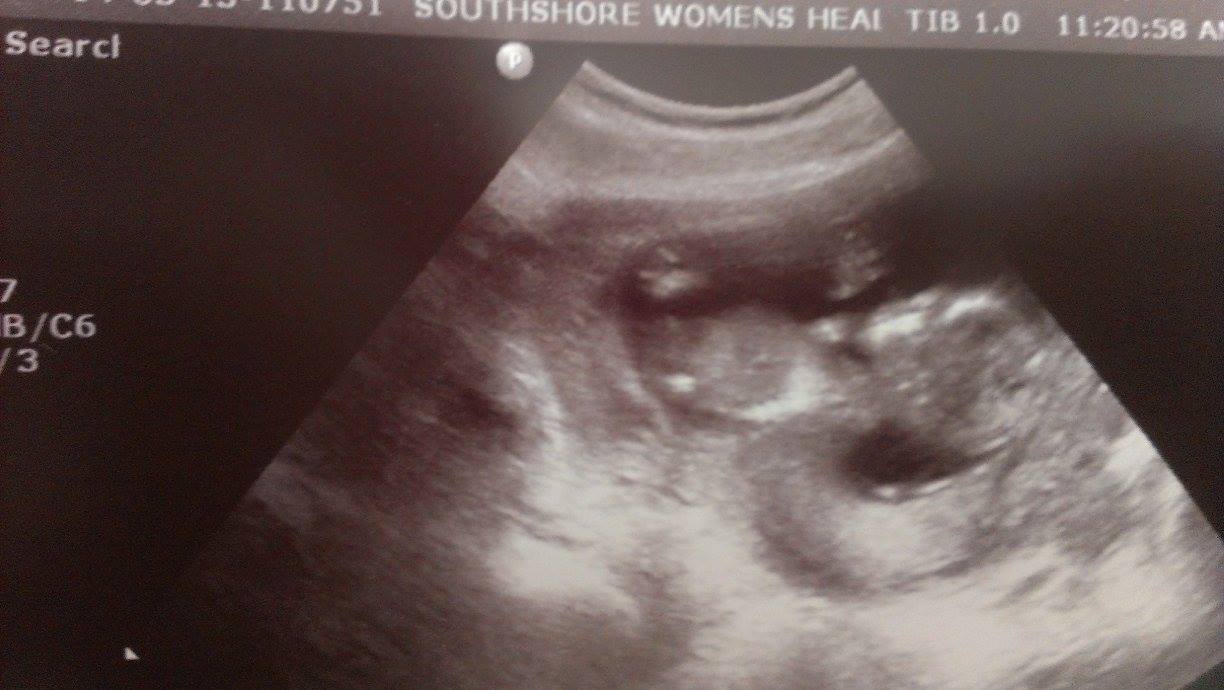

This is my ultrasound at about 14 weeks, I dont know if there is a nub and really just dont understand this skull theory! Can anyone please explain!

Attachment 18095